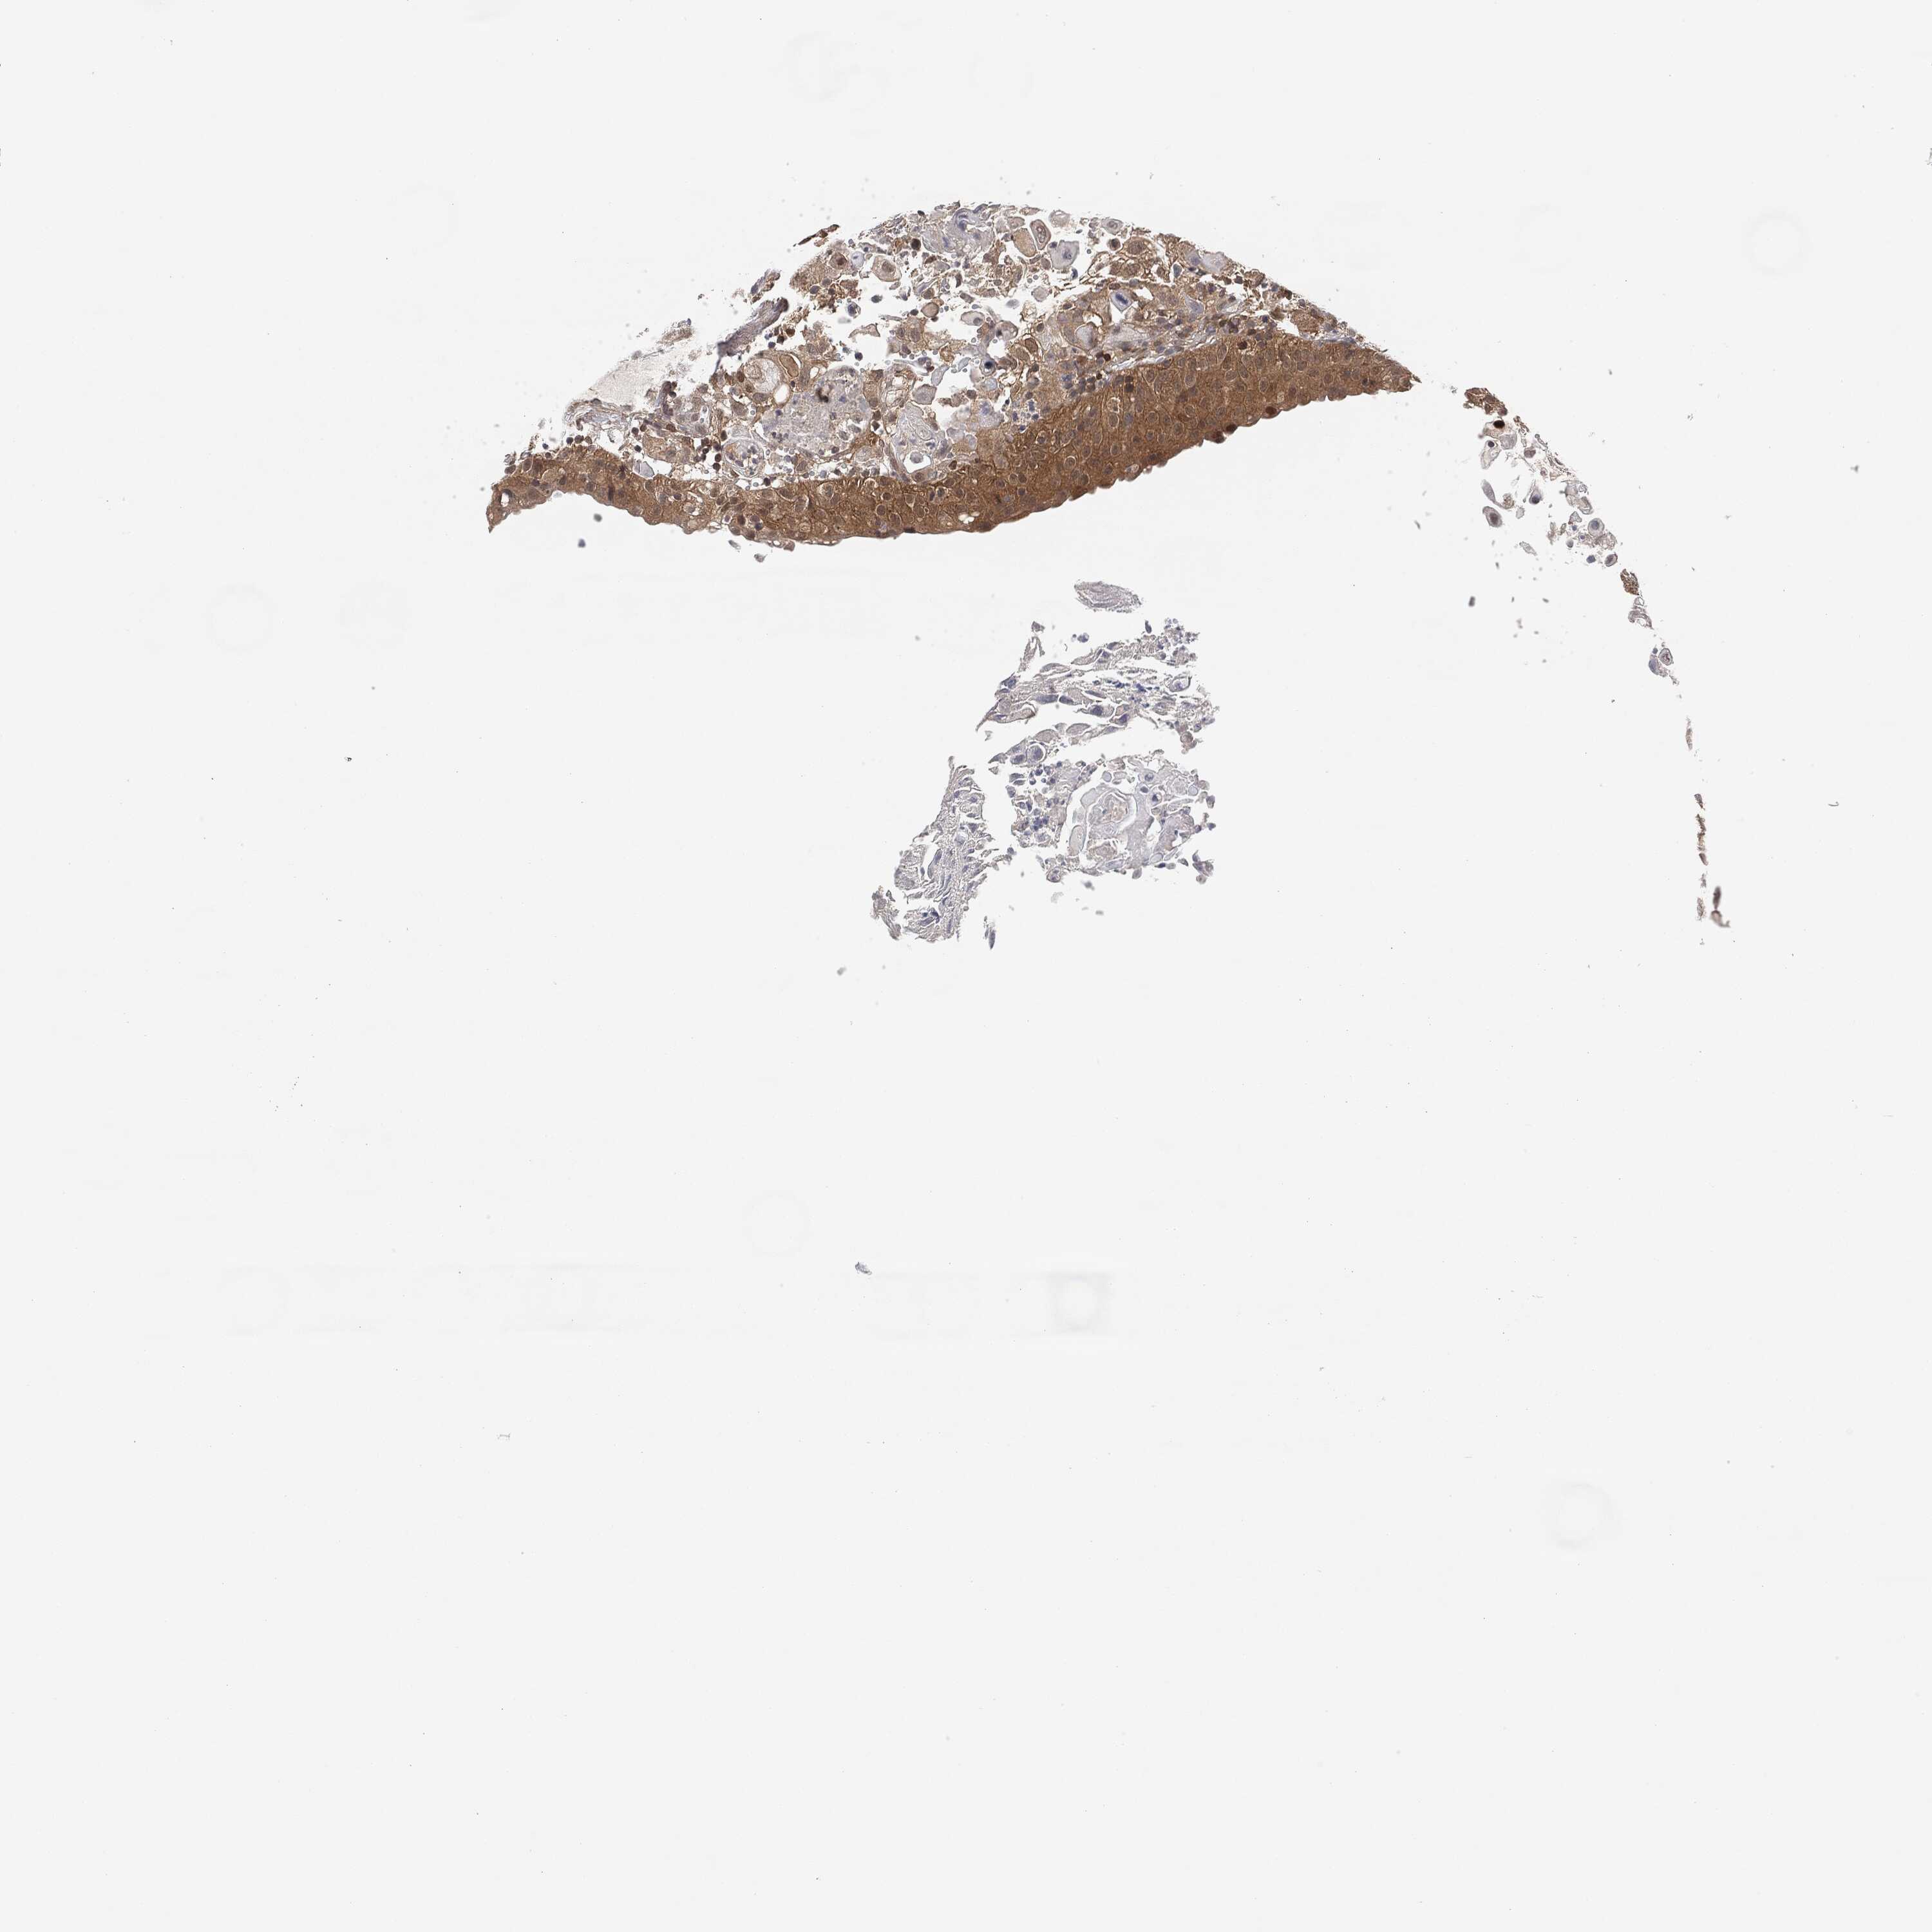

UROTHELIAL CANCER - Protein expressioni

A mouse-over function shows sample information and annotation data. Click on an image to view it in a full screen mode. Samples can be filtered based on level of antibody staining by selecting one or several of the following categories: high, medium, low and not detected. The assay and annotation is described here.

Antibody stainingi

Antibody staining in the annotated cell types in the current human tissue is reported as not detected, low, medium, or high, based on conventional immunohistochemistry profiling in selected tissues. This score is based on the combination of the staining intensity and fraction of stained cells.

Each image is clickable and will lead to virtual microscopy that enables deeper exploration of all samples and also displays staining intensity scores, fraction scores and subcellular localization as well as patient and tissue information for each sample.

Antibody CAB000102

Antibody CAB080442

Urothelial carcinoma, High grade

Urothelial carcinoma, Low grade

Adenocarcinoma, NOS